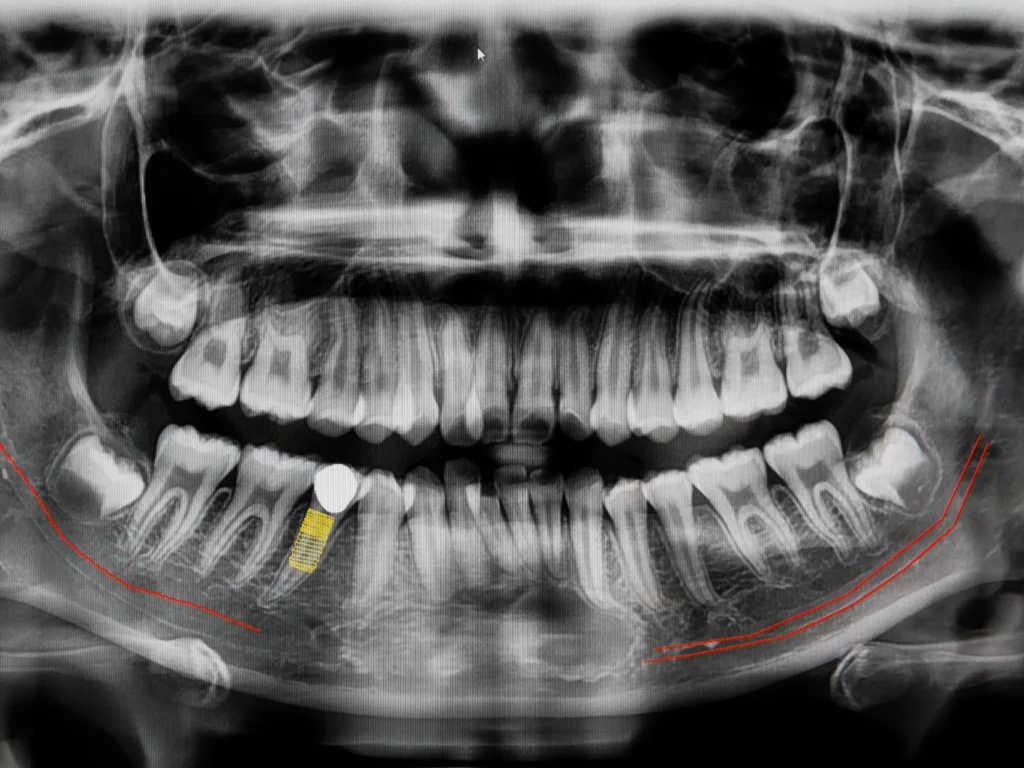

CBCT stands for ConeBeam Computed Tomography, which is a special type of digital x-ray scanner that dentists use to see a 3D image of your mouth and teeth.

The ConeBeam CT imaging system rotates once around your head while you stand or sit in a chair. The process is quick, simple, and completely painless. We use these scans to provide the best treatment in dental implants, root canals, diagnosis of dental and facial pain, etc.

We can evaluate your teeth and facial structures from literally every angle, in 3D, and in color! Routine x-rays, on the other hand, produce a single flat image with limited information.

You can have absolute confidence and satisfaction in the treatment you receive, knowing we’ve analyzed every problem with 3D technology.